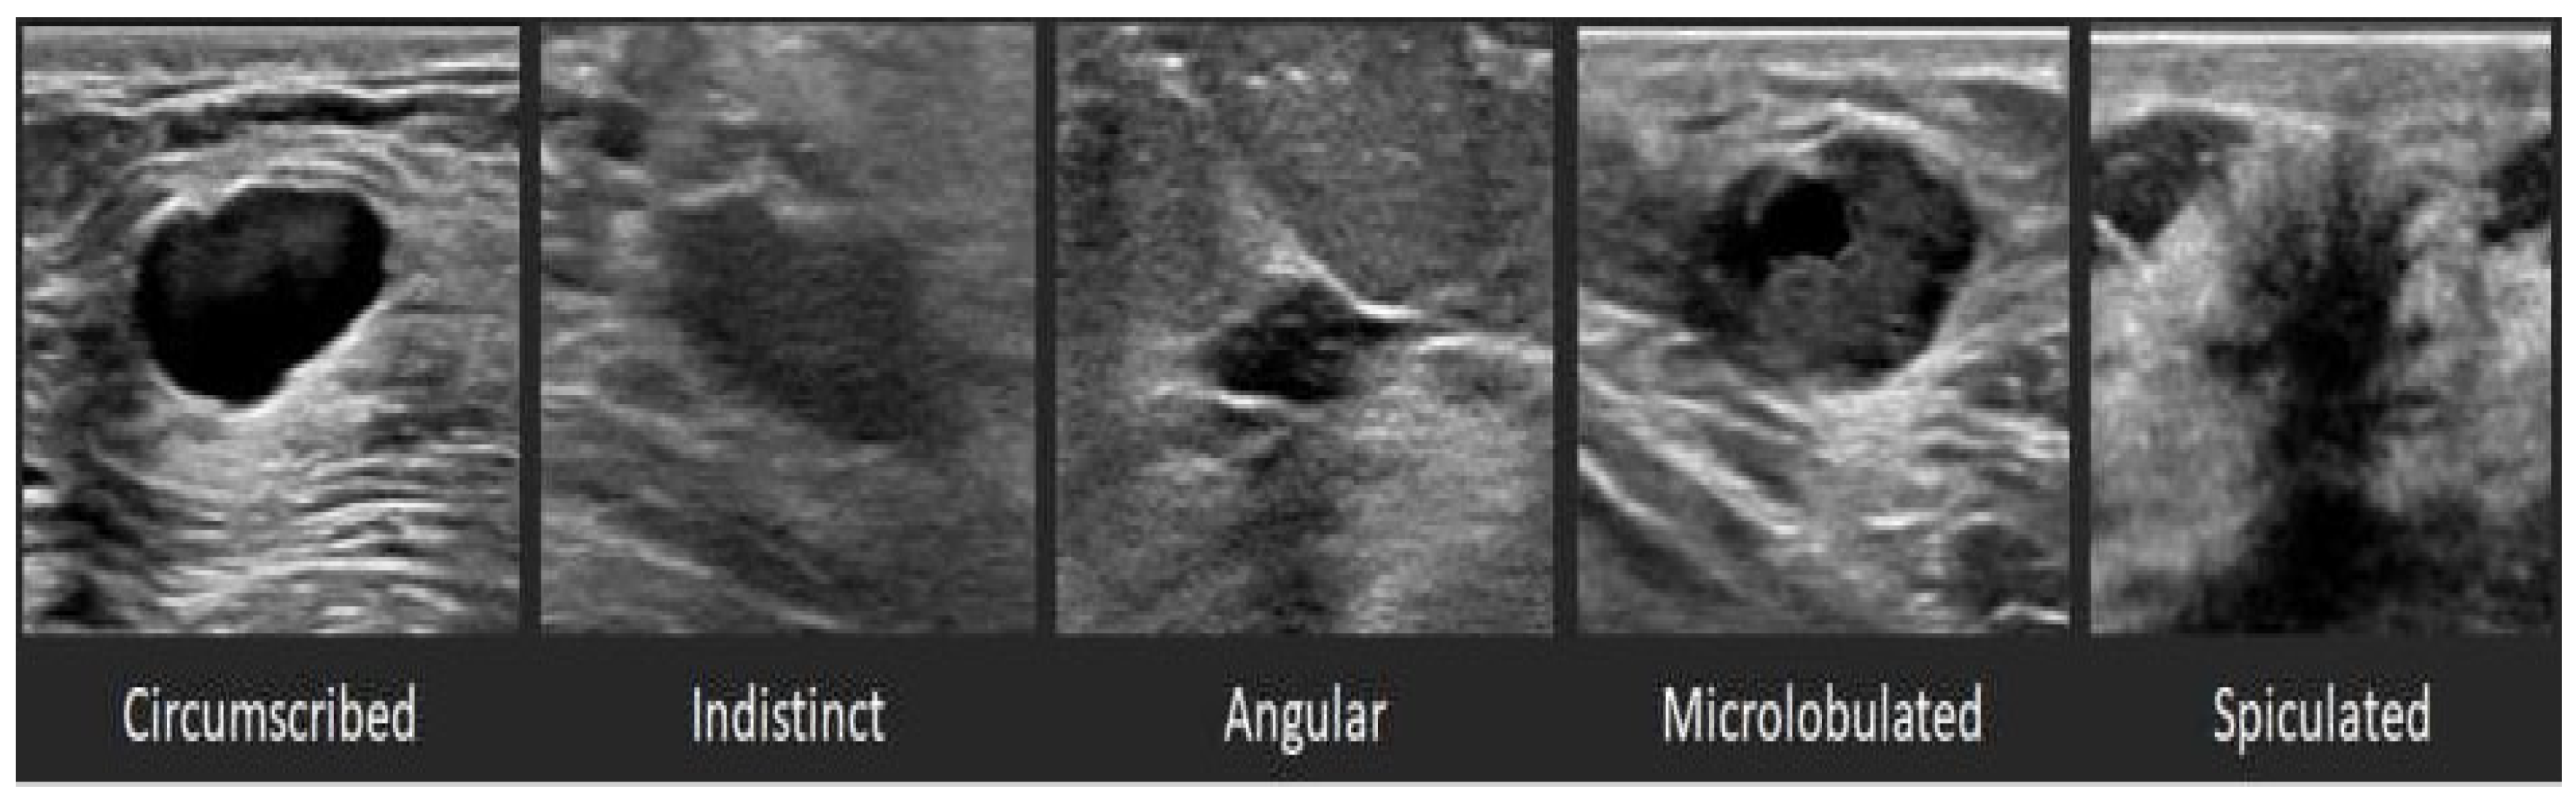

2.5. Tumor Malignancy Determination Using BI-RADS Category Information